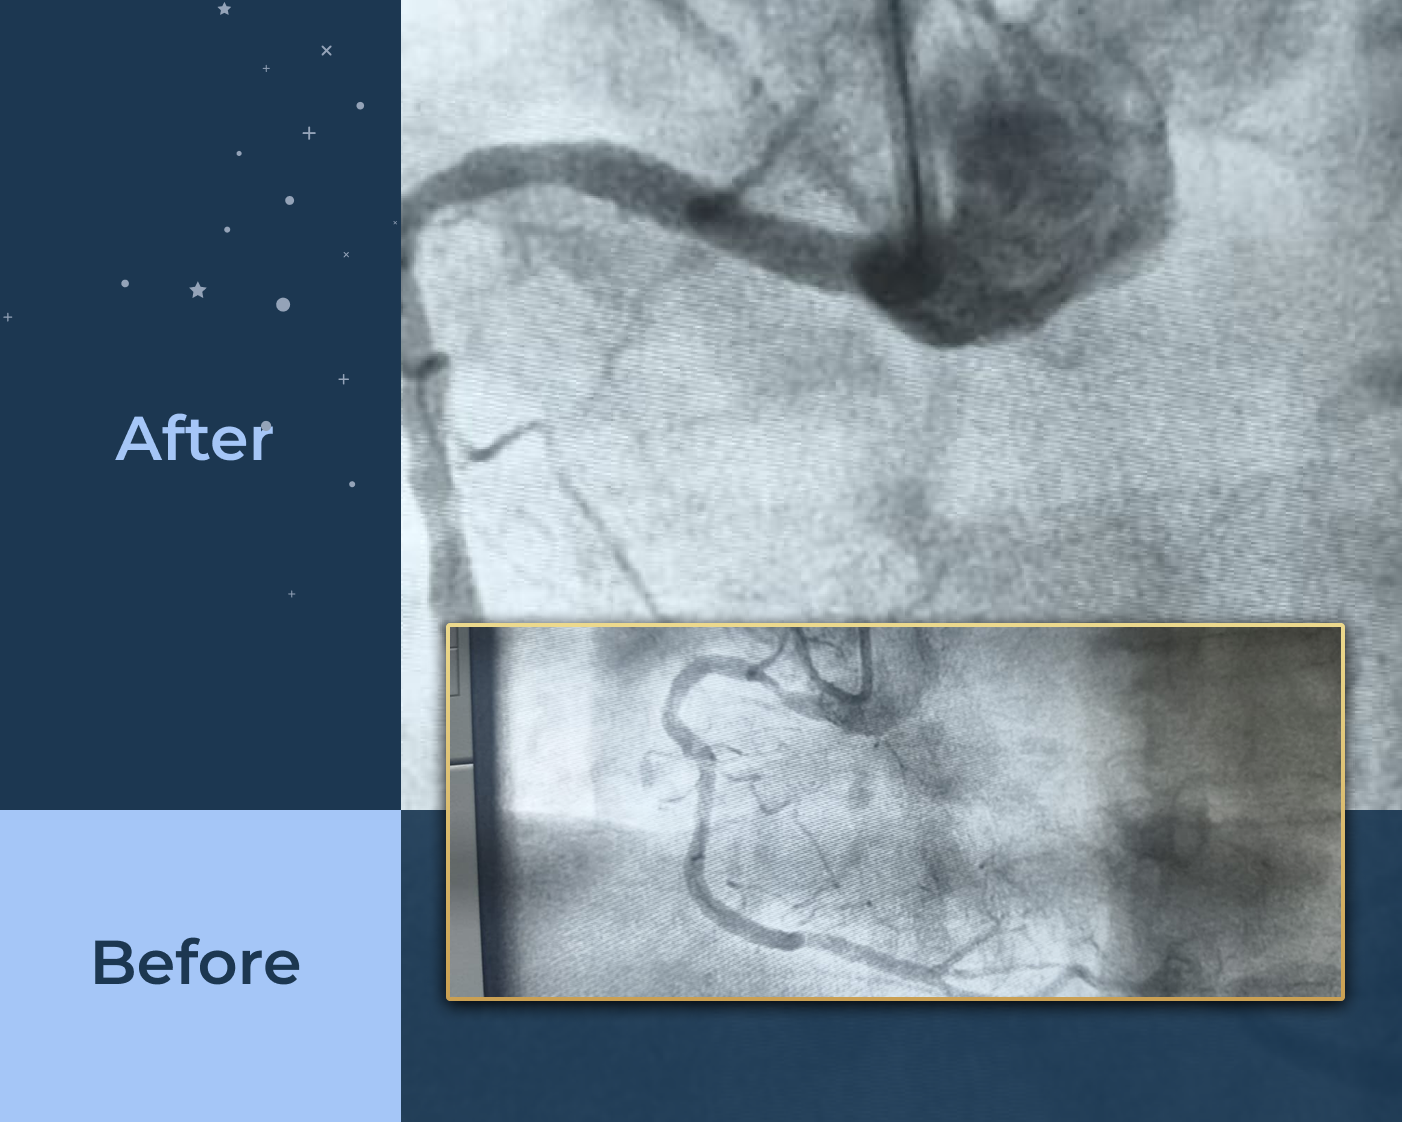

Interventions including Angiograms, Pacemaker Implantation, and Coronary Stenting.

Specialized stenting to restore blood flow with precision and monitoring for better heart function.

Specialized procedures including coronary, peripheral, and carotid stenting along with IVC filter devices.